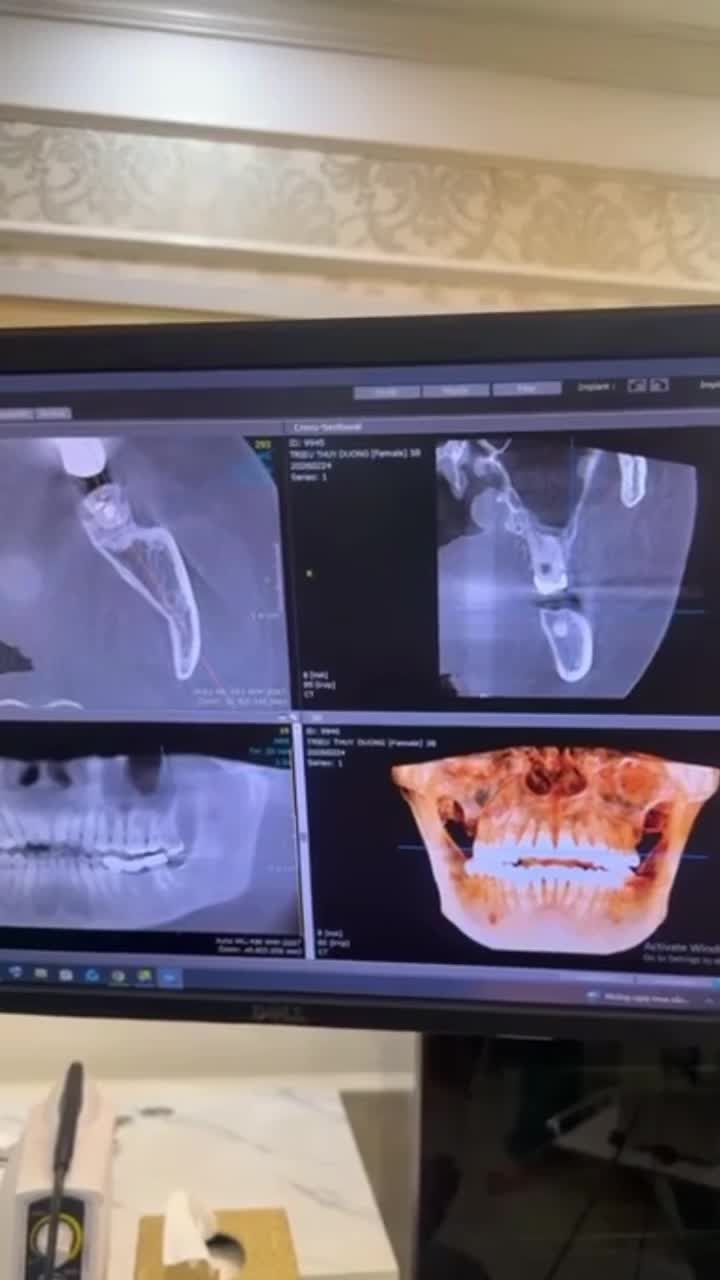

Nhổ răng khôn số 38 mọc lệch 45 độ đâm vào răng 7 cho bạn Hiền đang chỉnh nha tại Nha Khoa Thuỳ Anh

Ca nhổ răng số 37, 38 mọc lệch 90 độ gây sâu hỏng răng 37

Nhổ răng khôn số 38 mọc ngầm lệch 90 độ cho chị Ngọc tại nha khoa Thùy Anh.

Nhổ răng khôn 38, 48 mọc lệch 90 độ

Nhổ răng khôn số 48 mọc lệch 90 độ đâm vào răng 7 gây đau viêm tuỷ răng 7.